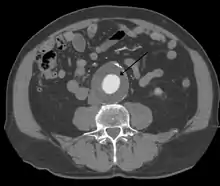

Abdominal aortic aneurysms (3,4 cm)

Abdominal aortic aneurysms (AAAs) are more common than their thoracic counterpart. One reason for this is that elastin, the principal load-bearing protein present in the wall of the aorta, is reduced in the abdominal aorta as compared to the thoracic aorta. Another is that the abdominal aorta does not possess vasa vasorum, the nutrient-supplying blood vessels within the wall of the aorta. Most AAA are true aneurysms that involve all three layers (tunica intima, tunica media and tunica adventitia). The prevalence of AAAs increases with age, with an average age of 65–70 at the time of diagnosis. AAAs have been attributed to atherosclerosis, though other factors are involved in their formation.[7]

CT reconstruction image of an abdominal aortic aneurysm

The risk of rupture of an AAA is related to its diameter; once the aneurysm reaches about 5 cm, the yearly risk of rupture may exceed the risks of surgical repair for an average-risk patient. Rupture risk is also related to shape; so-called "fusiform" (long) aneurysms are considered less rupture-prone than "saccular" (shorter, bulbous) aneurysms, the latter having more wall tension in a particular location in the aneurysm wall.[9]